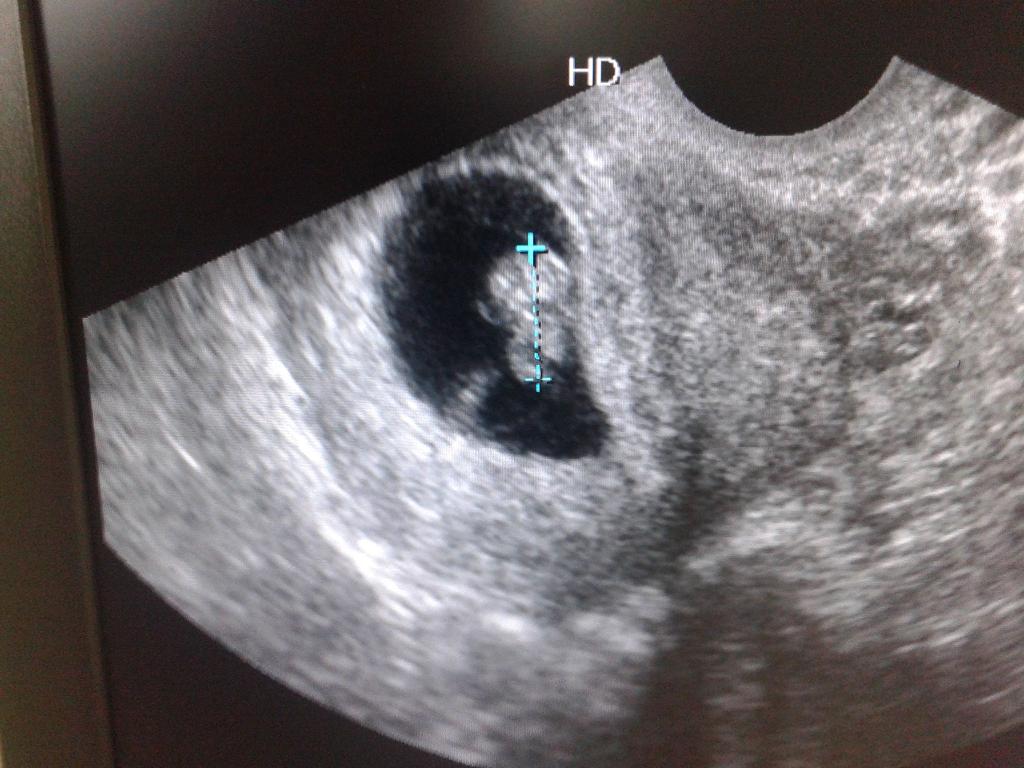

Jestem w domciu pomniejszylam zdj. Wzruszylam sie z mezem :) Dziewczyny mi sie wydaje ze dzidziolek macha mi <3 Jestem zakochana <3